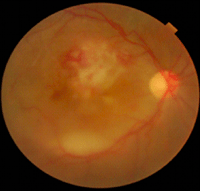

Enfermedad de Behçet

La OCT ha ayudado a entender los cambios de la retina neurosensorial en la uveítis por enfermedad de Behçet. Los vasos retinianos son el principal objetivo en la vasculitis oclusiva producida por esta enfermedad. Según los hallazgos por OCT se ha sugerido que el engrosamiento de la coroides es producida por una vasculitis primaria

23. La duración de la enfermedad de Behçet se ha correlacionado con el engrosamiento retiniano medido por OCT y con la agudeza visual

24. Unoki

et al24 documentaron cambios en la fóvea durante la remisión de la uveítis por enfermedad de Behçet (

Figura 19 y

Figura 20).

Figura 19. Hombre de 27 años que consulta por pérdida de visión en su ojo derecho. En la oftalmoscopia se observan áreas de vasculitis y edema con necrosis en polo posterior.

Figura 20. Hombre de 27 años que consulta por pérdida de visión en su ojo derecho. En la OCT hay un engrosamiento retiniano y un desprendimiento seroso de la retina.

Un hallazgo descrito es el defecto de la capa de fibras nerviosas en la uveítis por enfermedad de Behçet. Los defectos en cuña de la capa de fibras nerviosas peripapilar, corroborados por OCT, corresponden a defectos de campo visual en los pacientes con enfermedad de Behçet que no presentan afectación del sistema nervioso central. En estos casos el anillo neuroretiniano está preservado, a diferencia de lo que ocurre en los pacientes con patología glaucomatosa. Estos defectos aparecen típicamente tras la resolución de infiltrados retinianos en el polo posterior, sugiriendo un daño focal agudo en las capas de células ganglionares y la capa de fibras nerviosas

25.